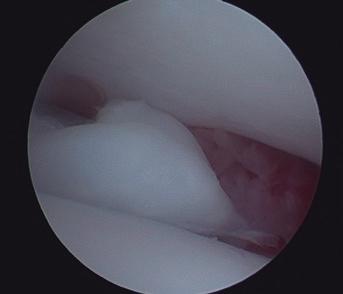

Se presenta el caso de una gata sometida a craneotomía supratemporal para exéresis de un menigioma, en la que se realizó un mantenimiento anestésico intravenoso para mantener una mayor estabilidad hemodinámica durante la cirugía.

Maine Coon, hembra castrada de 8 años, 3,5 kg y condición corporal 5/9, diagnosticada mediante resonancia magnética de una lesión extradural que afectaba a los lóbulos parietal, temporal y occipital (posiblemente meningioma) y que le producía un cuadro de circling, que en el momento de la anestesia estaba controlado gracias al tratamiento con dexametasona 0,15 mg/ kg/24 h. Como otros antecedentes clínicos, la paciente presentaba barro biliar, iniciándose el tratamiento con ácido ursodesoxicólico.